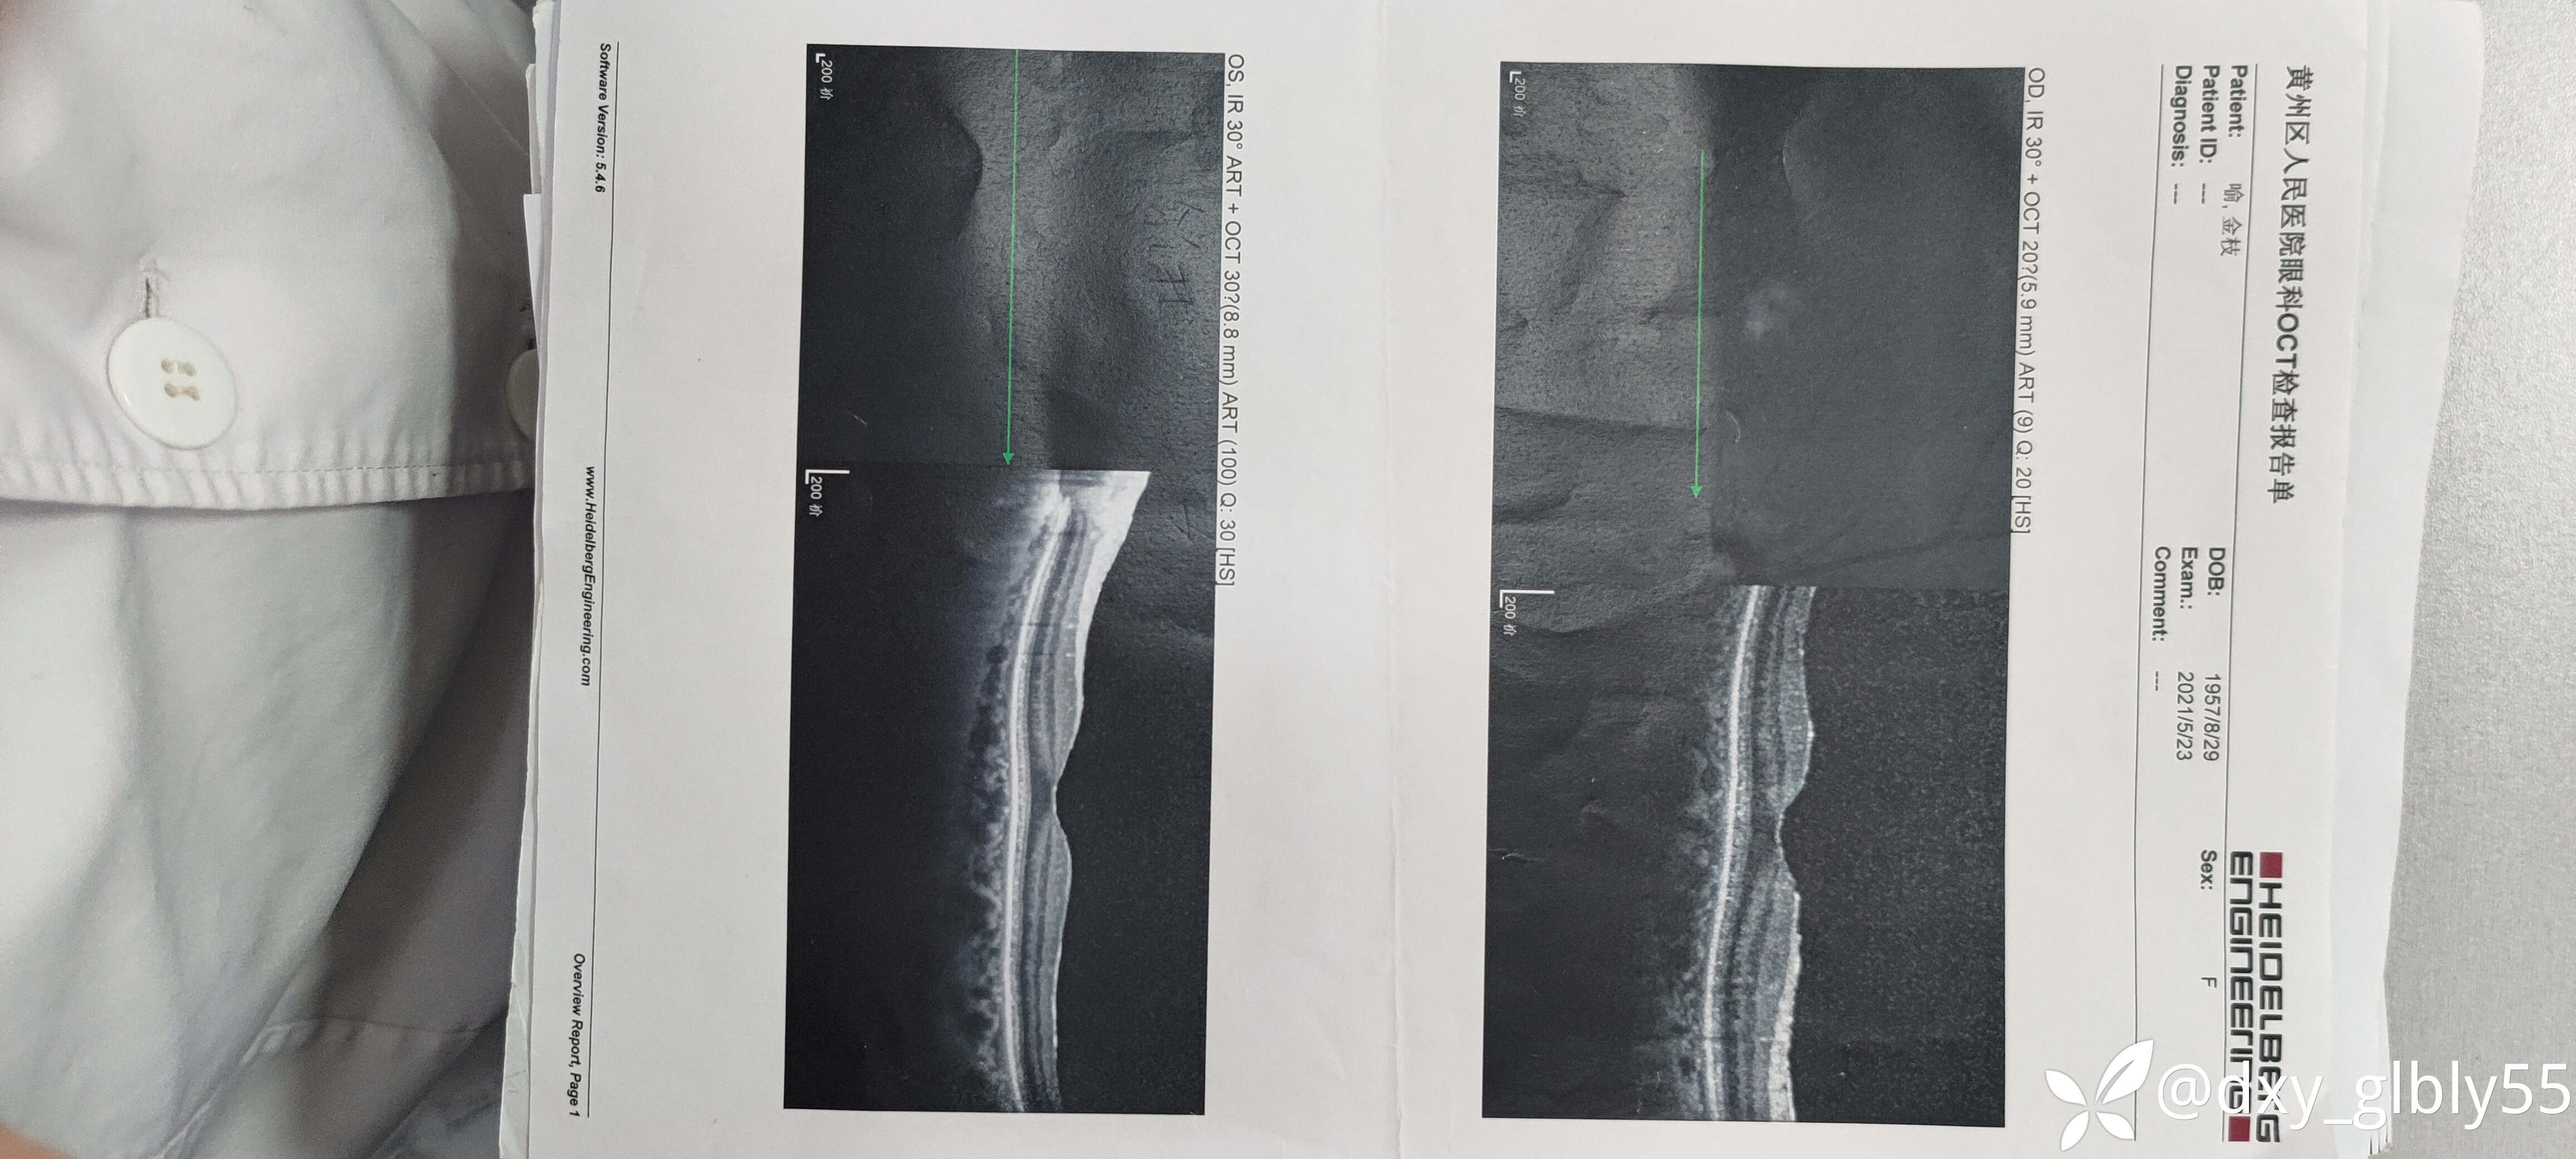

其他的辅助检查显示玻璃体轻度浑浊,未见网脱,出血,炎症反应等表现,oct查黄斑及视盘均未见明显异常。

就诊纪录以及一些有价值的特检结果我放在下面,除了电生理检查有异常在其他的特检没有表现明显的异常

一些特检结果我放在下面,请各位老师帮忙看一下,这个病人看了很多地方,很是苦恼